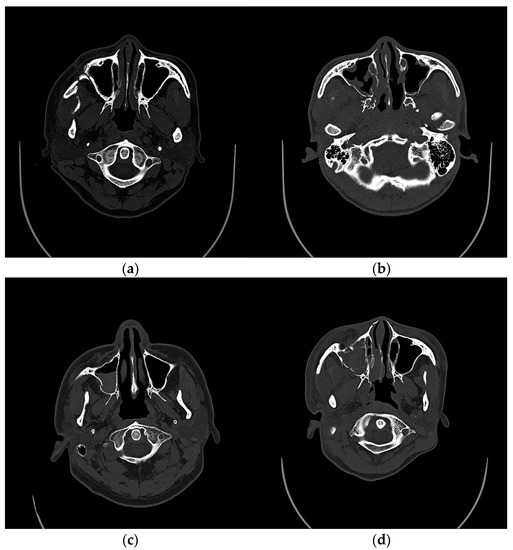

3. Results

4. Discussion